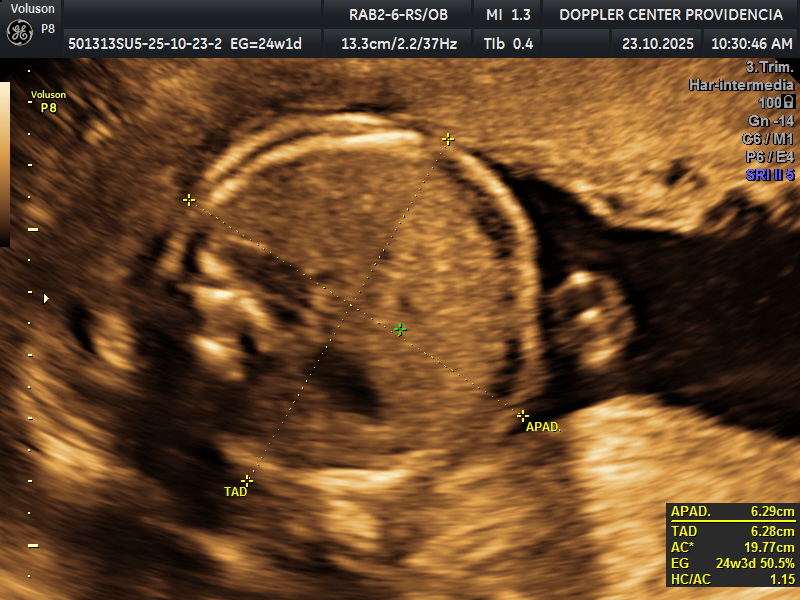

• Eco Doppler 22-24 semanas

• Eco Doppler III Trimestre